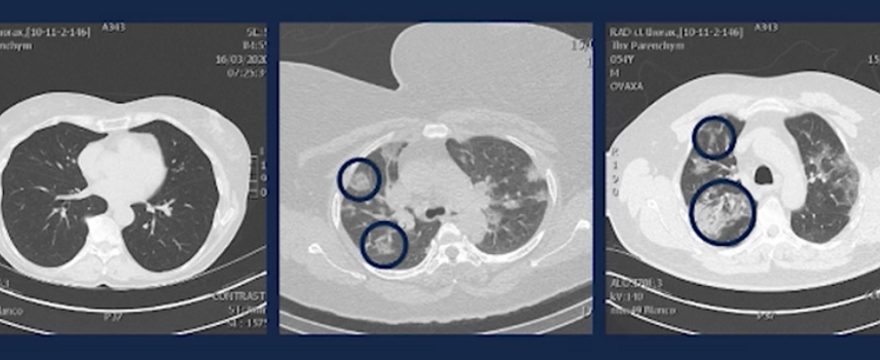

Belgijski lekarz pokazał, jak wyglądają płuca ludzi w wieku 20-50 lat zarażonych koronawirusem. To nie jest miły widok…

Dotychczas uważano, że koronawirus największe spustoszenie sieje wśród ludzi starszych. Tymczasem nawet młodzi ludzie w wieku 20-50 lat, muszą na siebie bardzo uważać. Mimo, że koronawirus w tej populacji wiekowej nie powoduje tak dużej śmiertelności, sieje on ogromne spustoszenie w płucach.

Ignace Demeyer  pokazał prześwietlenia płuc trzech różnych pacjentów z koronawirusem:

• na pierwszym zdjęciu widać zdrowe płuca,

• natomiast na drugim widać płyn, który wypełnia od 20 do 25 procent objętości pęcherzyków płucnych,

• trzecie zdjęcie przedstawia płuca, w których płyn zajmuje już 80-90 proc.,

• następny skan, to pacjent z zagrożeniem życia.